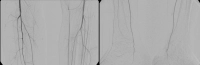

Exemplo de vídeo: TASC C → reconstrução aberta

Estágio IIb de DAP esquerdo (distância de caminhada inferior a 100 m). A DSA pré-operatória mostra:

- uma estenose subtotal da artéria femoral comum

- uma oclusão de segmento longo da artéria femoral superficial no canal adutor

- oclusões parciais das artérias da perna inferior